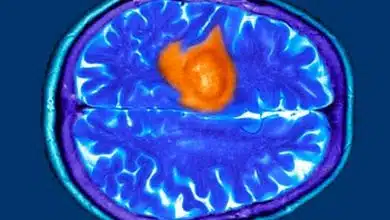

هفت نشانه پنهان تومور مغزی که ممکن است آنها را عادی بپندارید

بسیاری از علائم اولیه تومور مغزی، در ظاهر شبیه نشانههای روزمرهای مانند خستگی، استرس یا میگرن هستند و به همین…